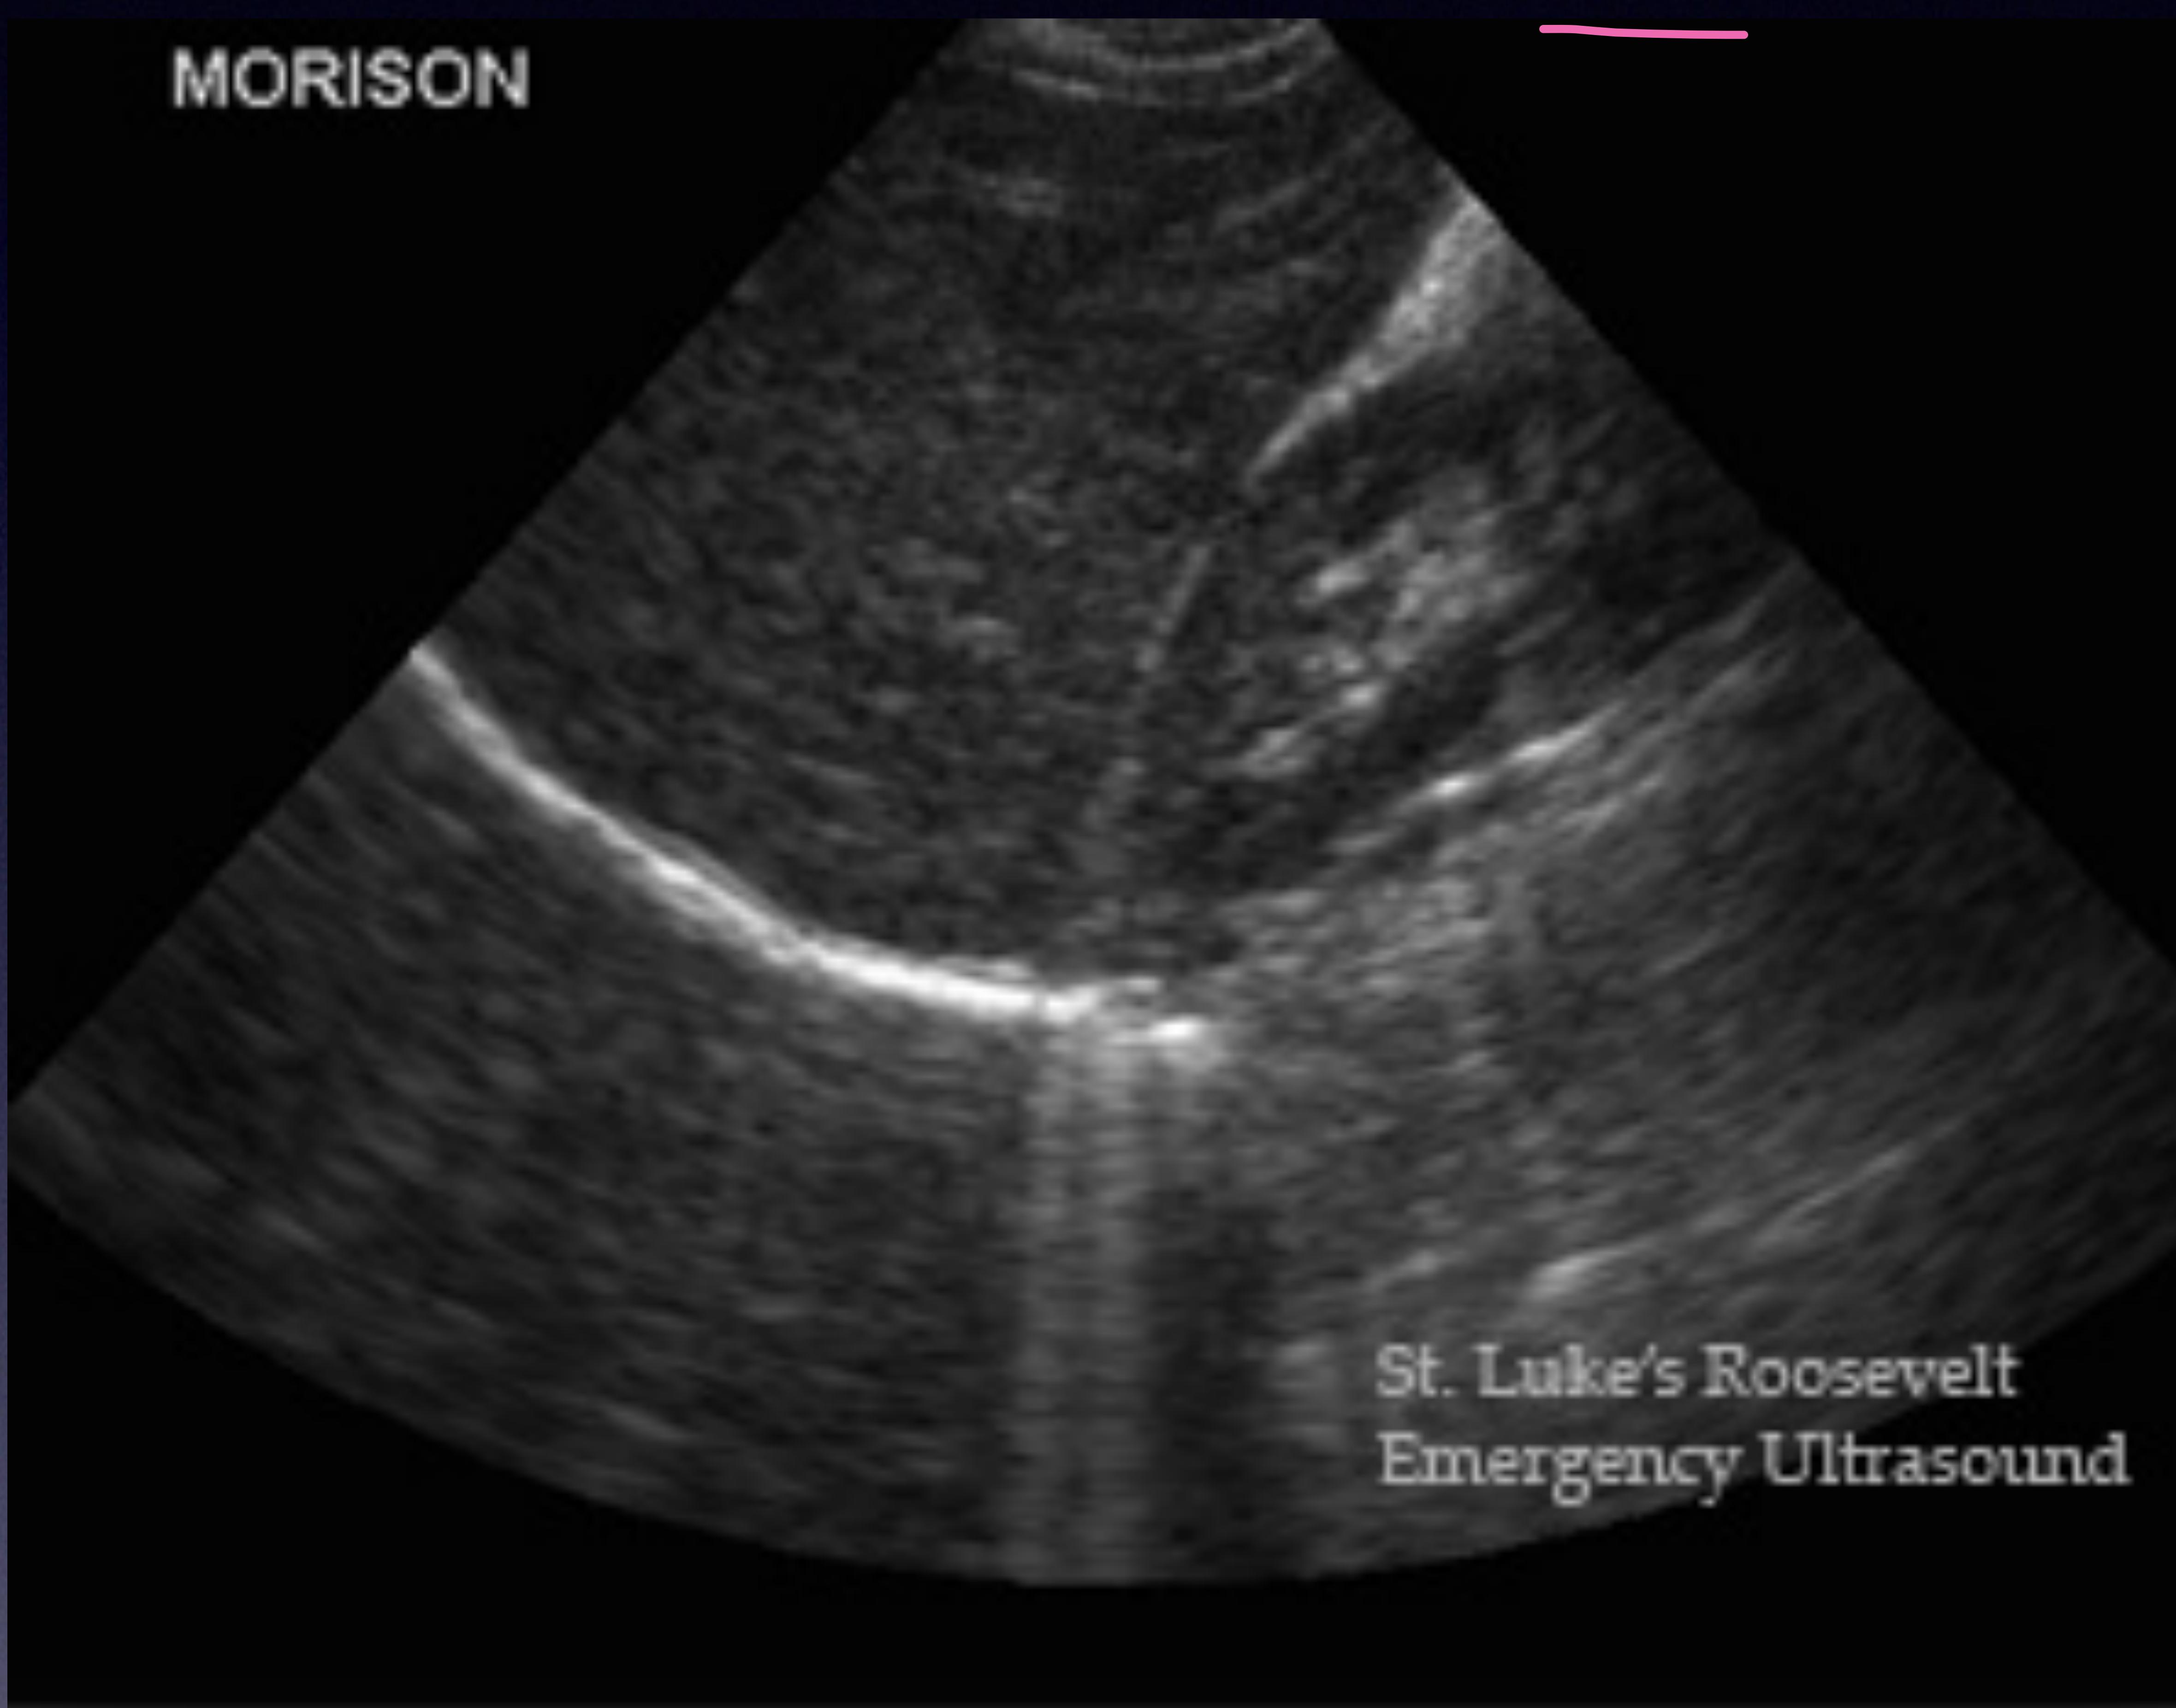

RUQ Scan (Morrison’s Pouch)

Liver and Kidney interface.

normal

Normal Morrison’s pouch.